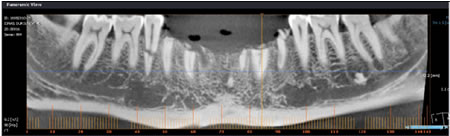

4.1 Standart Panoramik Röntgende Ölçümler

4.2 Aproksimal Panoramik Röntgende Ölçümler